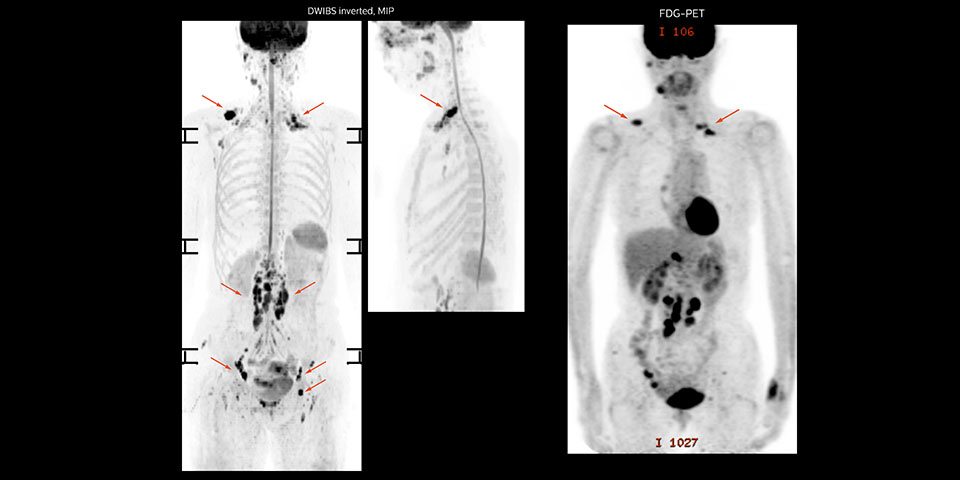

A 61-year-old female with a malignant lymphoma underwent an MRI exam with whole body diffusion weighted imaging (DWIBS) as well as PET. On the images shown, the resolution of DWIBS is better than PET, which allows visualization of the small pelvic lesions and almost no distortion is seen in the neck area.